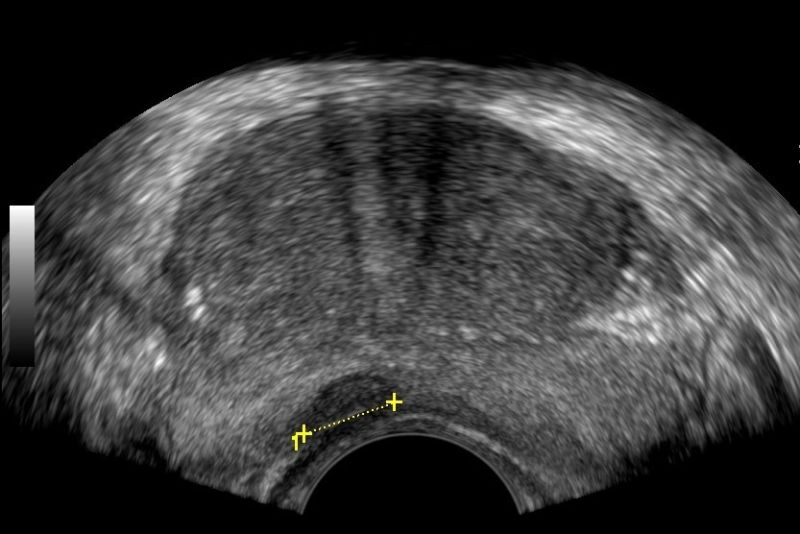

- Prostate: It allows for a detailed assessment of the prostate's morphology and size.

- Examination: The exam begins with a Lower Abdominal Ultrasound (suprapubic) and continues with the transrectal exam after urination. The transrectal ultrasound is performed using a special probe inserted into the rectum through the anal sphincter. This method provides a comprehensive evaluation of the prostate's morphology.